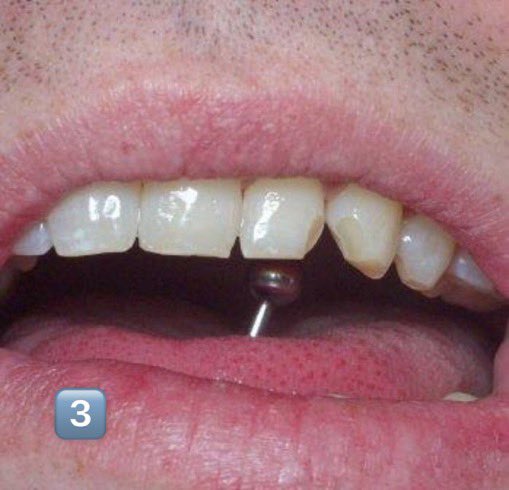

مع انتشار استعمال الحلق في منطقة الشفة واللسان.. أجد من واجبي التحذير من مضارها على المدى البعيد كإنحسار اللثة1️⃣أو تفرق الأسنان4️⃣والمدى القريب كالإلتهابات الحادة2️⃣وكسور الأسنان 3️⃣

فوجود هذه الاجسام المؤذية في مناطق دقيقة وحساسة غير مستحب